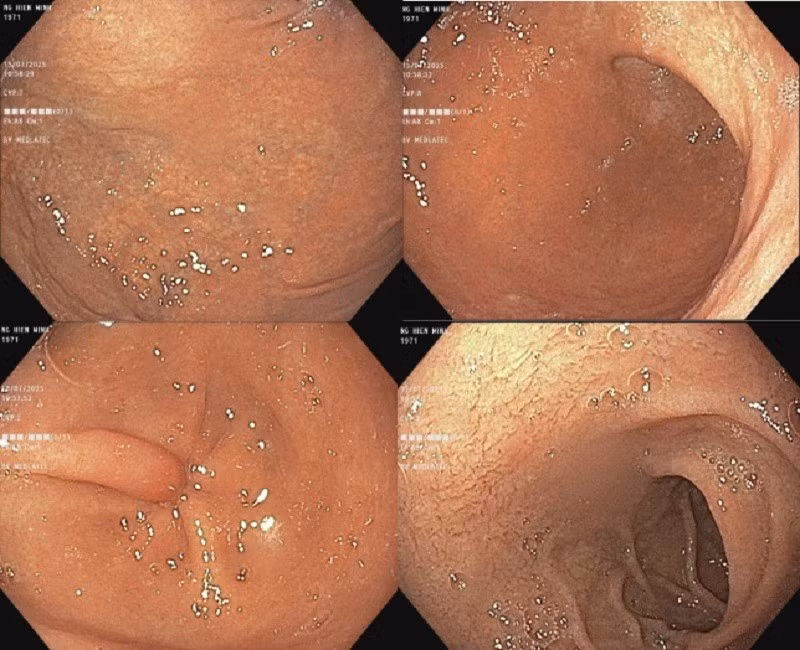

Đối với triệu chứng đau âm ỉ quanh vùng gót chân trái, kết quả chụp Xquang cho thấy, hình ảnh gai xương gót chân trái - nghi ngờ viêm cân gan chân mạn tính.

Xquang thấy hình ảnh gai xương gót bàn chân trái/Ảnh BV medlatec